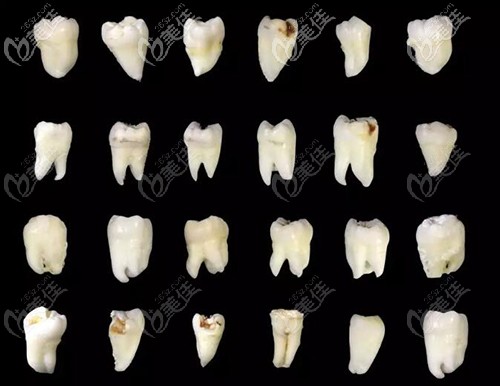

想必很多人多少都有牙齒問題,其中智齒是比較難決定要不要拔掉的,有人說我的智齒橫著長(zhǎng)七八年了也不疼,應(yīng)該沒事,其實(shí)這種才更應(yīng)該選擇拔掉。